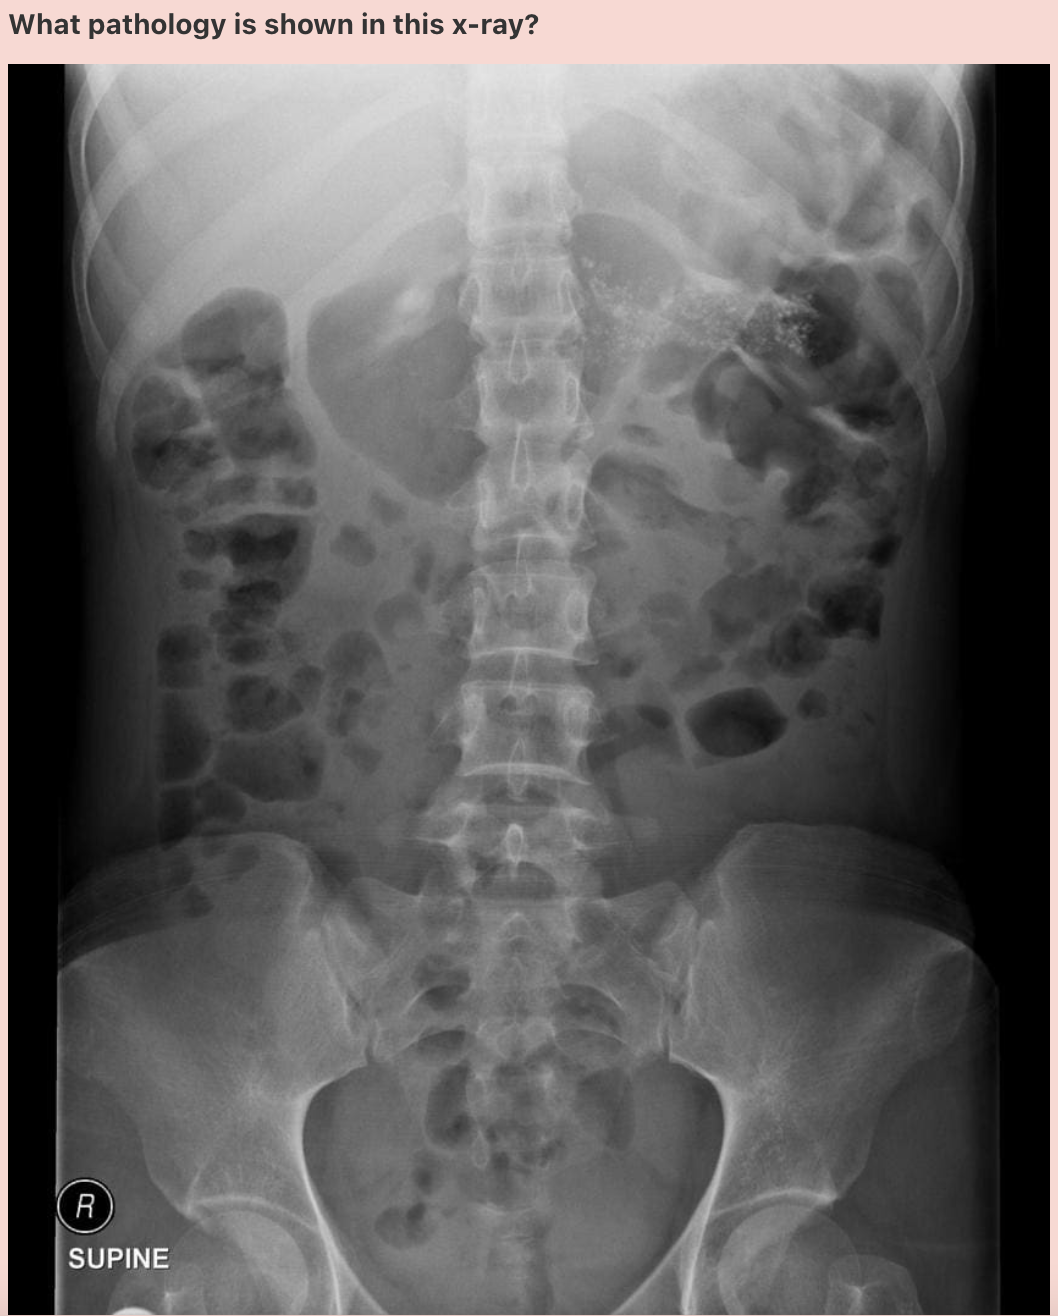

**Answer: Dilated small bowel** ## Footnote The bowel is visible as there is gas (black) within. You can tell that it is the small bowel as it is centrally located and valvulae conniventes can be seen throughout. The loops measure \>3 cm in diameter, therefore, they are dilated. ***_Note: The height of an adult vertebral body is approximately 4 cm. You can use this as a quick comparison to estimate the diameter of the bowel._***